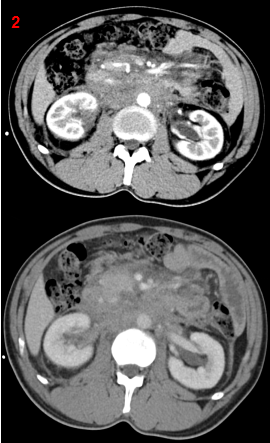

增強CT示腹膜后局部腹主動脈及其分支近端周圍餅狀軟組織腫塊(圖2),考慮腹膜后纖維化。建議完善IgG4相關檢查。